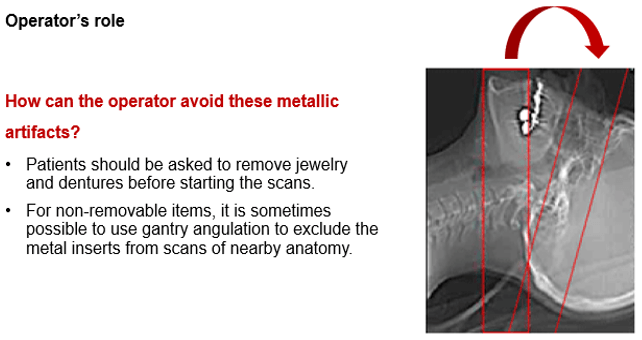

As part of an operator’s role, patients should be asked to remove jewelry and dentures before starting the scans. This assists in avoiding some metallic related artifacts.

For non-removable items such as dental fillings and joint prosthesis, it is sometimes possible to use gantry angulation to exclude the metal inserts from scans of nearby anatomy.